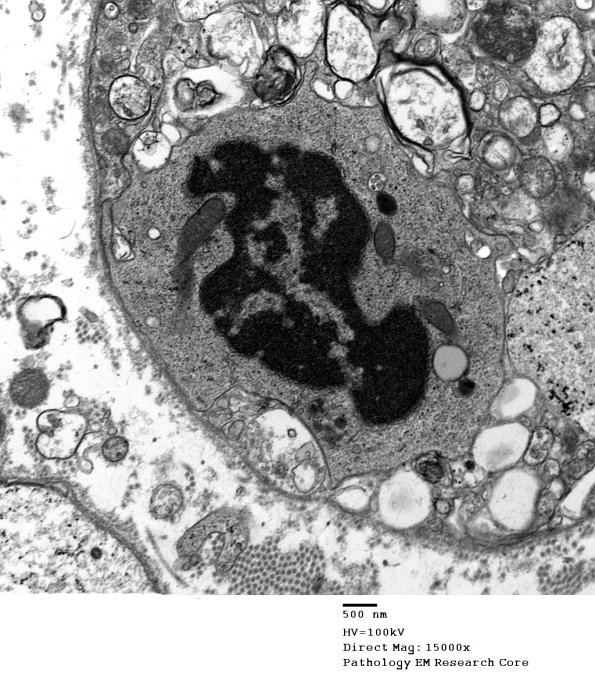

3B2,3 Higher magnification images show delicate short processes of the macrophage (arrows, 3B3).